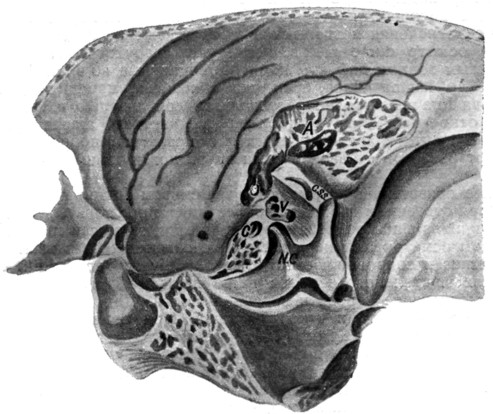

КТ анатомия сосцевидного отростка: особенности и показания